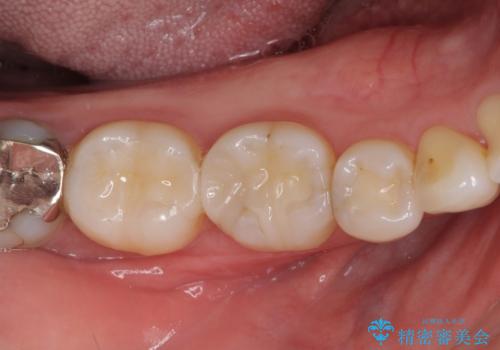

話をする度に相手の視線が銀歯に注がれている気がしているとのことでしたが、目立つ銀歯を自然な色合いに仕上げることができ、患者様には大変満足していただきました。